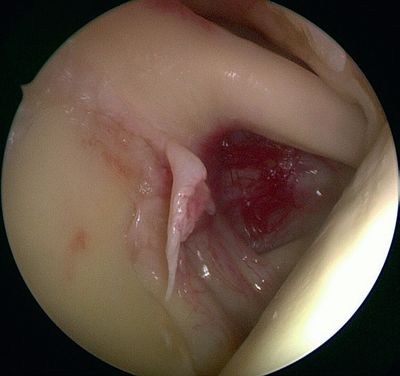

Walch et al. developed the theory of isolated posterosuperior impingement by publishing a series of 17 arthroscopies performed in athletes who demonstrated pain in the cocking phase but lacked concomitant instability. They explain this symptomatology by mechanical impingement repeated at 90% of abduction, maximum external rotation and retropulsion (maximum extension), between the greater tubercle and the posterosuperior glenoid rim, causing partial tears in the posterosuperior rotator cuff and the facing glenoid labrum (Figure, Movies).[11]

Posterosuperior impingement of Walch.

The appeal of this theory is that it is validated by simple observation when reproducing cocking and retropulsion movements under arthroscopic control, revealing the tears by repeated contact (Video).